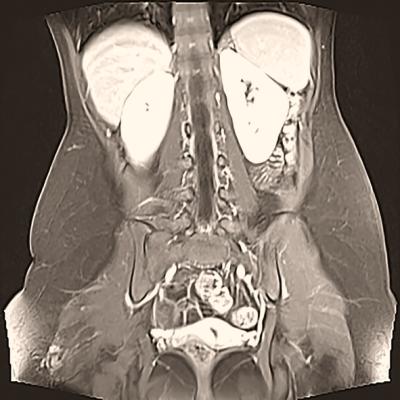

Getty Images